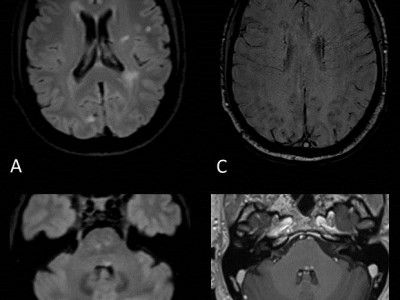

For neuromyelitis optica spectrum disorder (NMOSD), one would see mostly infratentorial lesions near the fourth ventricle. The linear, T2-hyperintense lesions may be contiguous with cervical transverse myelitis, according to the poster authors. They added that other key MRI findings include the appearance of diencephalic lesions in proximity to the third ventricle and rostral midbrain.

With Neuro-Behcet disease, Muga and colleagues said T2-weighted MRI will show edematous lesions that have a hyperintense appearance while one will note microhemorrhages on susceptibility-weighted imaging and contrast enhancement of acute lesions on T1-weighted MR images. Optic neuritis and intracranial sinus thrombosis are common with Neuro-Behcet diseases, according to the poster authors. Muga and colleagues also noted that infratentorial atrophy may result from chronic Neuro-Behcet disease.

When it comes to brain stem lesions caused by multiple sclerosis, Muga and colleagues said radiologists will see well-circumscribed, ovoid lesions that are found in the dorsal and ventral brain stem. More likely to occur in the pons than the medulla, these lesions are hyperintense on fluid-attenuated inversion recovery (FLAIR) sequences and T2-weighted MRI images, according to the poster authors.